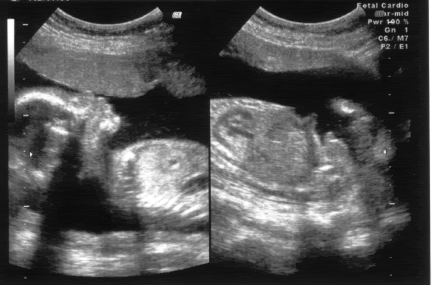

Seeing the Ultrasound Scan of Seth Benjamin Goh